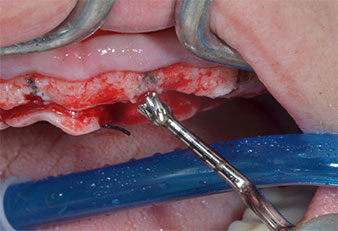

Ein flammenförmiges, diamantiertes piezochirurgisches Instrument (Piezomed I1) wurde verwendet, um die Implantatpositionen zu markieren und die Pilotpräparationen durchzuführen (Abb. 3). Dabei wurde darauf geachtet, eine Auf- und Abbewegung mit reduzierter Leistung, voller Spülung und niedrigem Druck (unter 300 g) anzuwenden. Als Nächstes wurde ein Pilotinstrument (Piezomed I2A/I2P) zur initialen Erweiterung der Implantatlager auf einen Durchmesser von 2 mm verwendet (Abb. 4), gefolgt von einem 3-mm-Instrument (Abb. 5).

Ultraschallmarkerinstrument Piezomed

Abb. 3: Die Präparation mit dem Ultraschallmarkerinstrument Piezomed I1 erfolgt mit einer Auf- und Abbewegung, parallel zur Längsachse des Arbeitsteils.